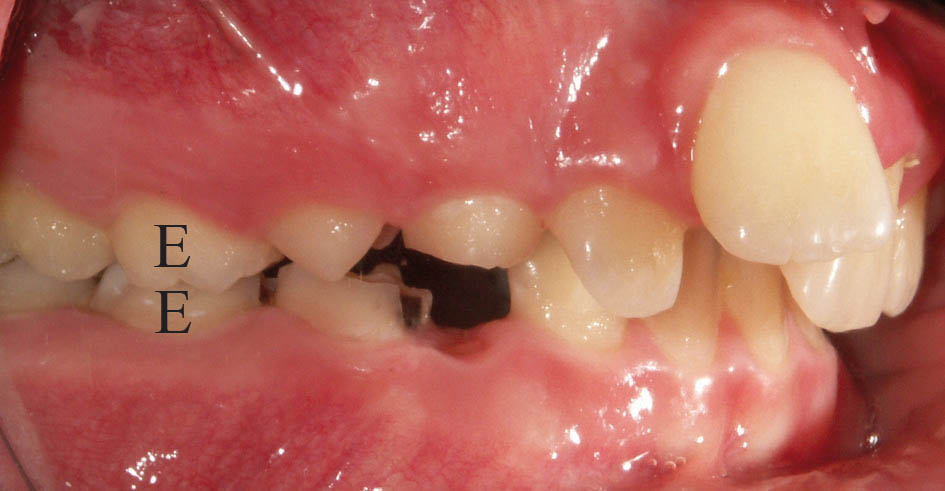

با پالاتالی شدن انسیزورهای بالا وقتی بیمار دندانهای خود را میبندد (در حالت CR) انسیزورهای پائین با انسیزورهای بالا نوک به نوک میشوند و تماس دندانهای خلفی از بین میرود (شکل 22-5 و 23-5).

شکل 22-5: توانایی نوک به نوک بستن یک بیمار کلاسIII (بیمار کلاسIII کاذب نامیده میشود)

شکل 23-5: نوک به نوک شدن انسیزورها در CR

در این مواقع بیمار برای رسیدن به حداکثر تماس بین دندانی (CO) مندیبل را جلو میآورد تا خلفیها به یکدیگر تماس پیدا کنند (انحراف قدامی مندیبل) و شما یک کراس قدامی (شکل 24-5) و ایجاد یک رابطه کلاسIII مولری را میبینید.

شکل 24-5: انسیزورهای بالا و پایین بیمار در زمان بستن دندانها نوک به نوک میشوند. بیمار برای رسیدن به حداکثر تماس بین دندانی (CO) مندیبل را جلو میآورد و به همین دلیل به او کلاسIII کاذب میگوییم.

شکل 25-5: جابجایی قدامی مندیبل جهت رسیدن به حداکثر تماس دندانی(CO)

منجر به نمایش کراس قدامی میشود.